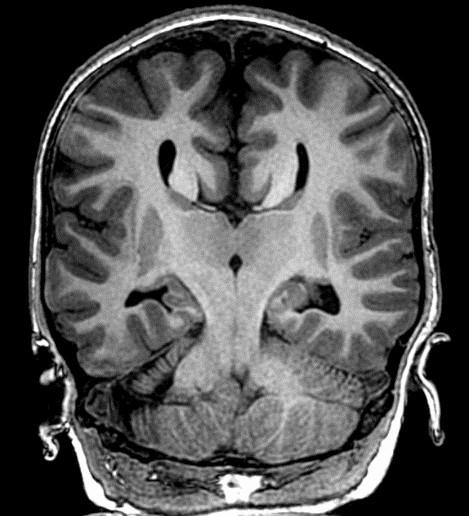

Remember to start with Sweep the Midline… Where is the anterior commissure?

Always finish the sweep looking for second anomaly…

Parallel ventricles

Radial or pallisading gyri in sagittal plane

Colpocephaly

Longhorn or Viking helmit frontal horns

High riding 3rd vent

“Keyhole” temporal horns

Vascular anomalies: “wandering ACAs”

All 3 commissures are absent.

Cingulate gyrus (black arrows) “mirrors” the development of the corpus callosum.

Enlarged HC connects fornices, not cerebral hemispheres